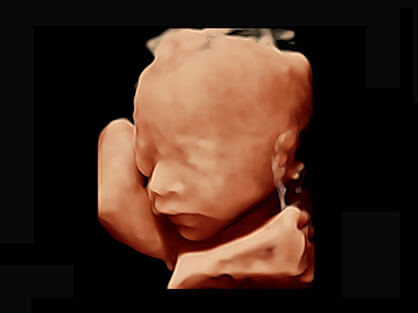

作为P系列家族成员之一,P40 Plus采用狗万官方网站高端超声系统平台——极光,并以时尚秀丽、小巧灵动的外观设计绽放出灵动之韵、科技之美。高端平台的使用保证了P40 Plus优质的基础图像;完备的高级功能可满足您全身应用的基本需求;丰富的探头配置、多样的高级4D成像及分析软件为您日益增多的妇产应用需求提供丰富的诊疗方案。

可同时显示组织结构表面和内部的轮廓信息,达到透视效果,为临床提供更丰富的诊断信息。

宽频带腹部凸阵探头和腹部容积探头、大角度腔内探头和腔内容积探头、独特的生殖专用曲柄探头,为妇产应用提供全面诊疗方案。